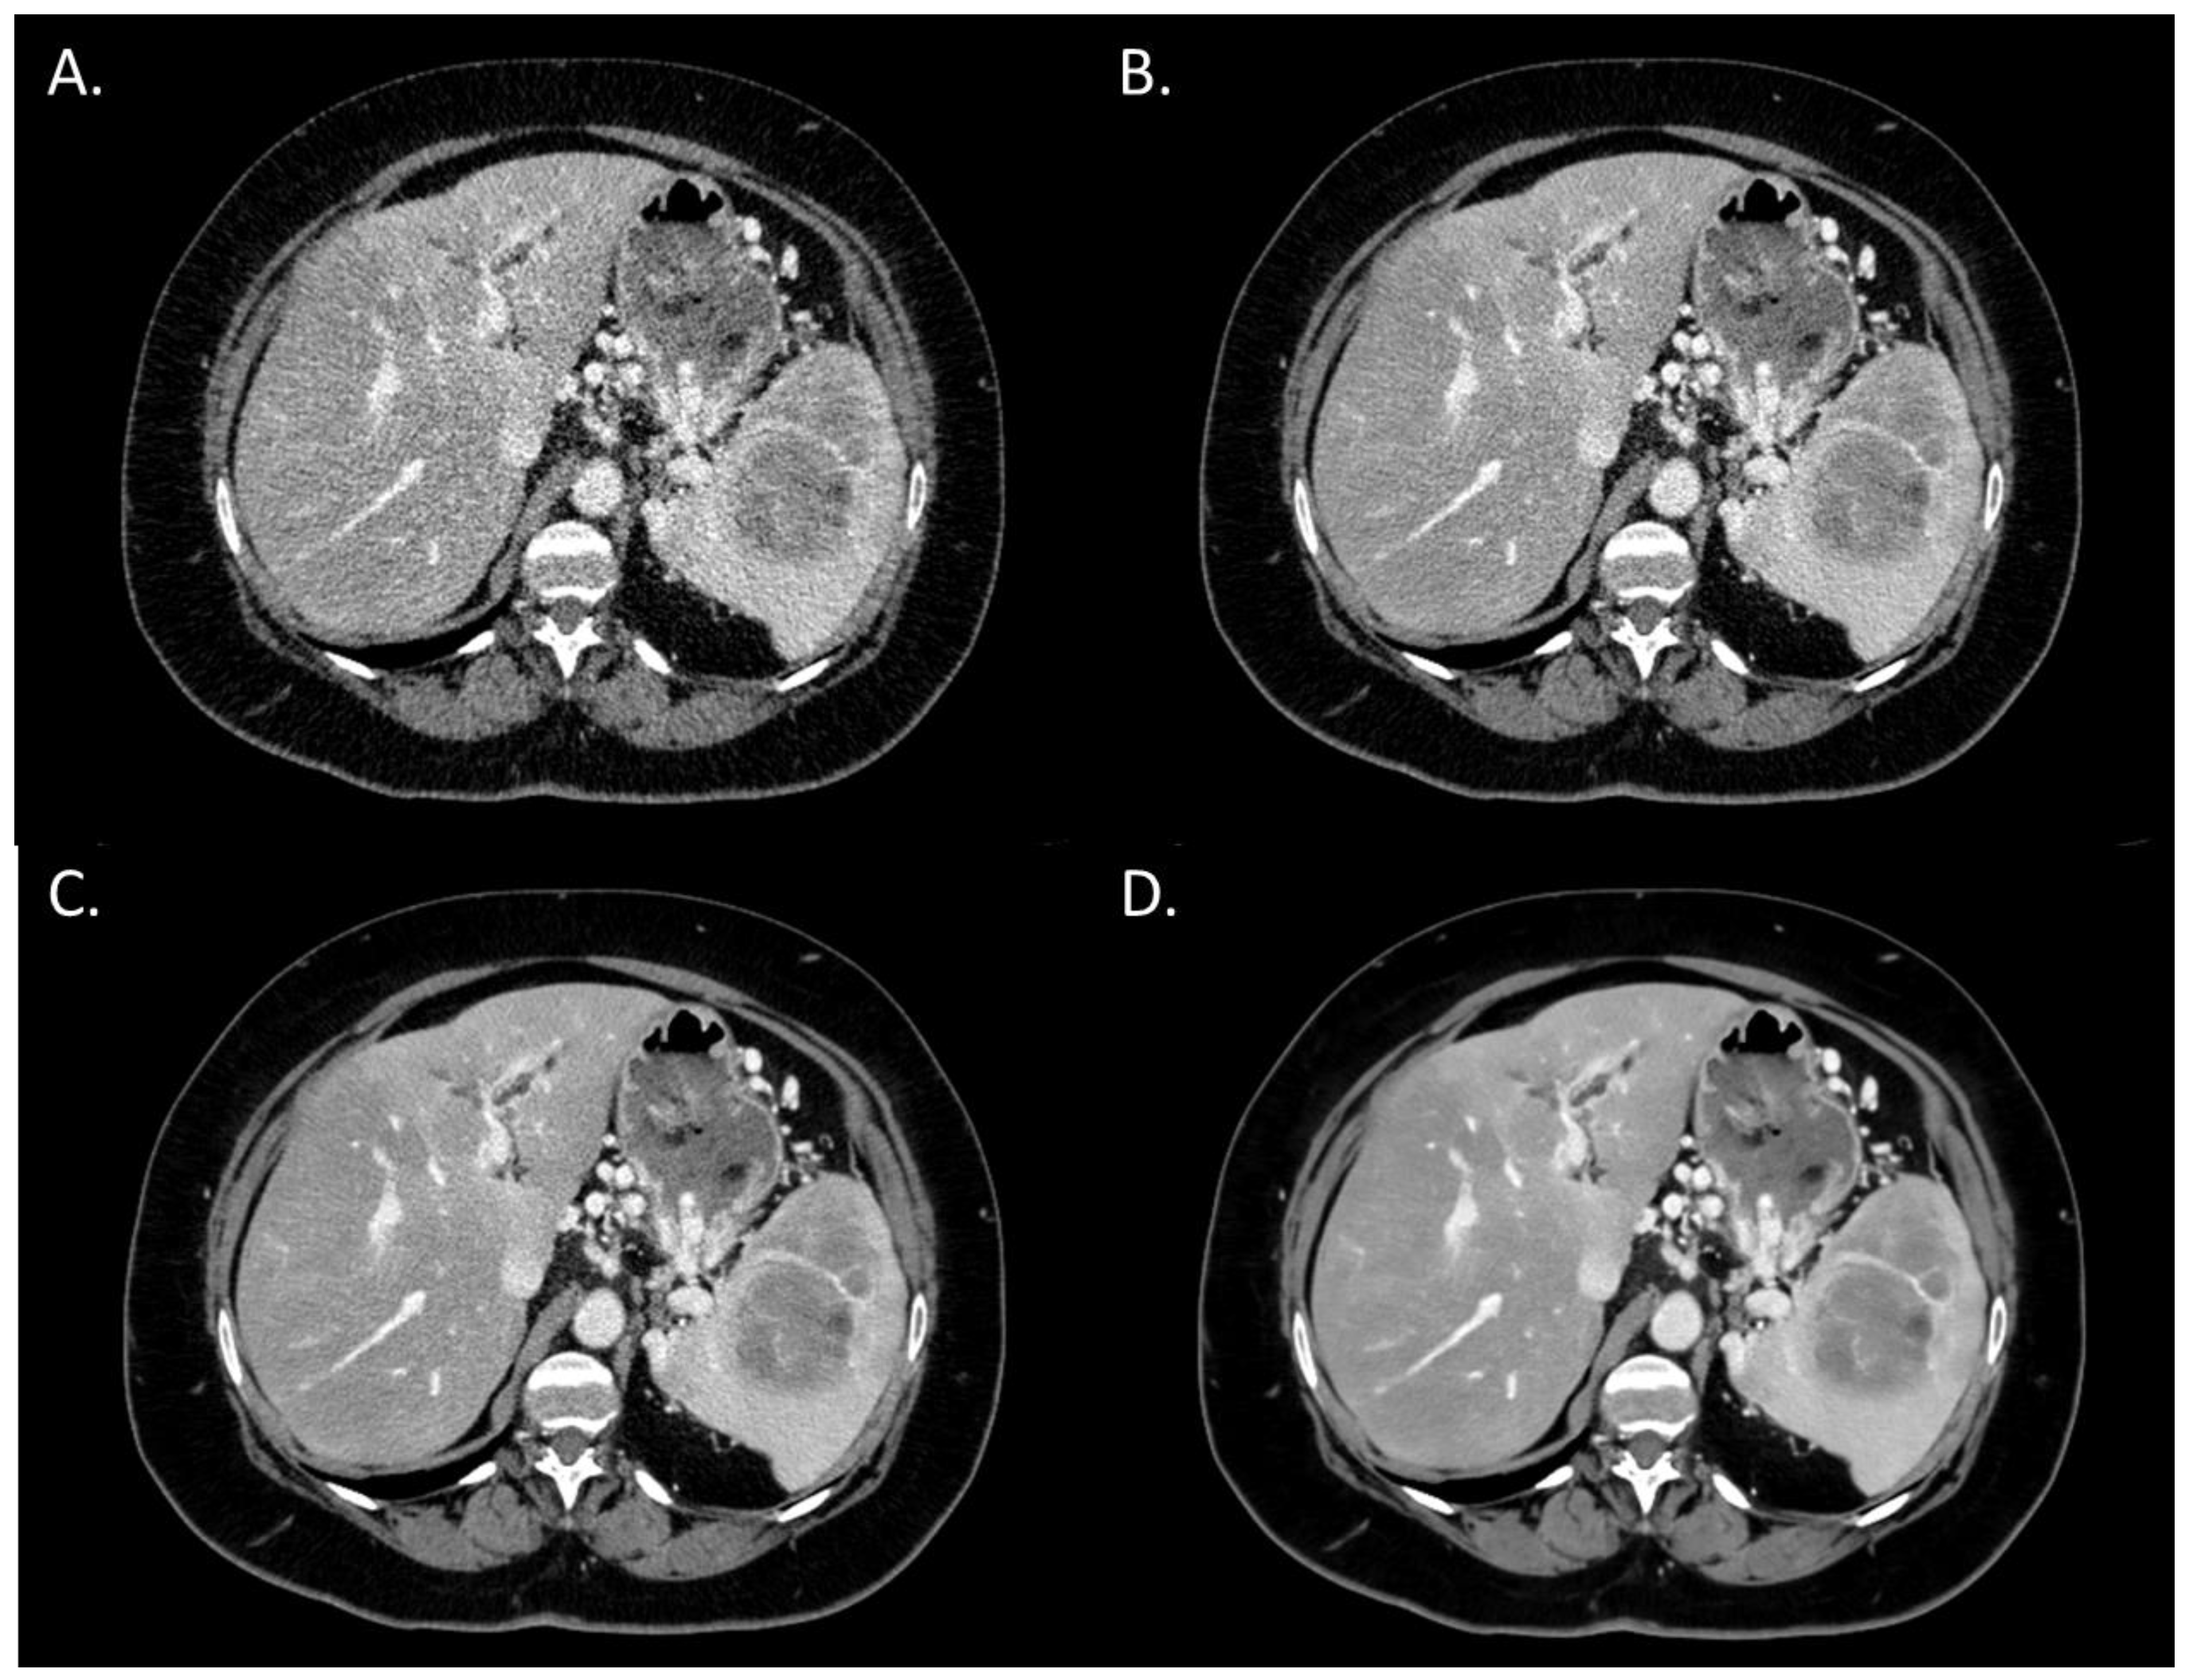

The overall image quality score significantly increased from i4 to the Standard level (p < 0.05) and from the Standard to the Smoother level (p < 0.05) (Figure 1). Both radiologists rated the overall image quality as “Interpretable despite moderate artefacts or noise” for all patients with i4. For all DLR levels, the overall image quality was rated as “Fully interpretable with mild artefacts or noise” or as “No artefacts or noise”. Agreement between the two radiologists was “excellent” for the Standard and Smooth levels. For i4 and the Smoother level, the two radiologists rated the images with the same score for all patients.

Figure 1.

Overall image quality of abdominal CT images (WL: 60 HU; WW: 360 HU) of a woman with pancreatic cancer and abdominal metastatic lesions (63 years old; SSDE: 9.09 mGy; average scan size 32.2 cm). (A) iDose4 level 4; average overall image quality score: 2.5; (B) Precise Image, Standard; average overall image quality score: 3; (C) Precise Image, Smooth; average overall image quality score: 4; (D) Precise Image, Smoother; average overall image quality score: 4.